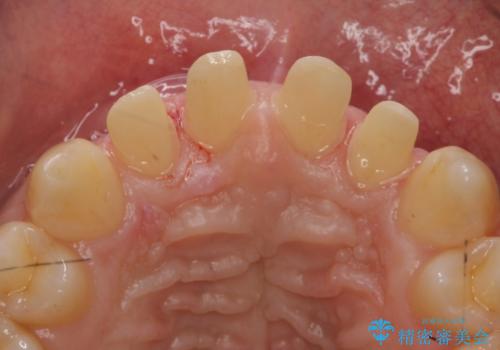

前歯のすき間 セラミックで綺麗に 最短で治療

- 前歯のすき間を気にして来院。

矯正治療か、セラミックで最短で治すかの選択肢を提示し、セラミックで治すことにしました。

全て神経は取らずに、削りました。